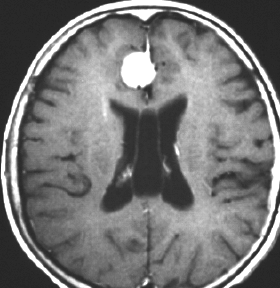

4歳の時に低線量頭蓋照射を受けていますが,医療関係の仕事について自立していた33歳の女性です。仕事中に記憶が飛ぶという症状がでて,周囲からおかしいと言われて受診しました。右の扁桃体のところ(左側のMRI)に海綿状血管腫ができていて,側頭葉てんかん(欠伸発作)を生じていました。バルプロ酸の投与で発作は止まって職場復帰しています。